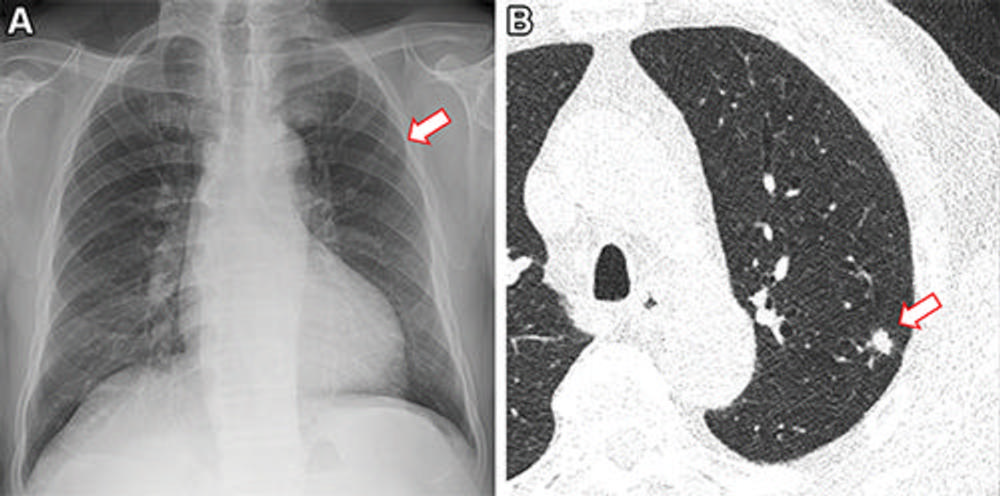

Figure 4. Images in a 73-year-old man who underwent chest radiography and low-dose CT for health checkup purposes and was allocated to the non–artificial intelligence (AI) group. (A) Frontal chest radiograph shows a small nodular opacity (arrow) in the left upper lung zone, which was missed by the designated reporting radiologist. (B) Axial, noncontrast, low-dose chest CT scan shows a 9-mm solid nodule (arrow) in the left upper lobe. The nodule showed low metabolism at PET and decreased in size at follow-up CT. It was confirmed to be an inflammatory nodule.